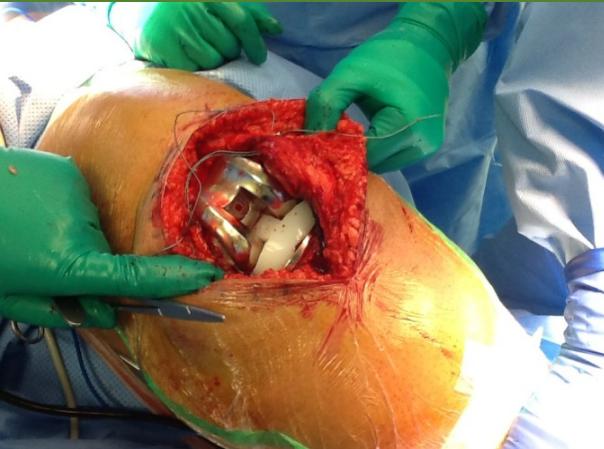

Surgical Considerations

- Timing: When conservative measures fail

- Options:

- Arthroscopy (selective cases)

- Osteotomy (young patients with unicompartmental disease)

- Total knee arthroplasty (end-stage disease)